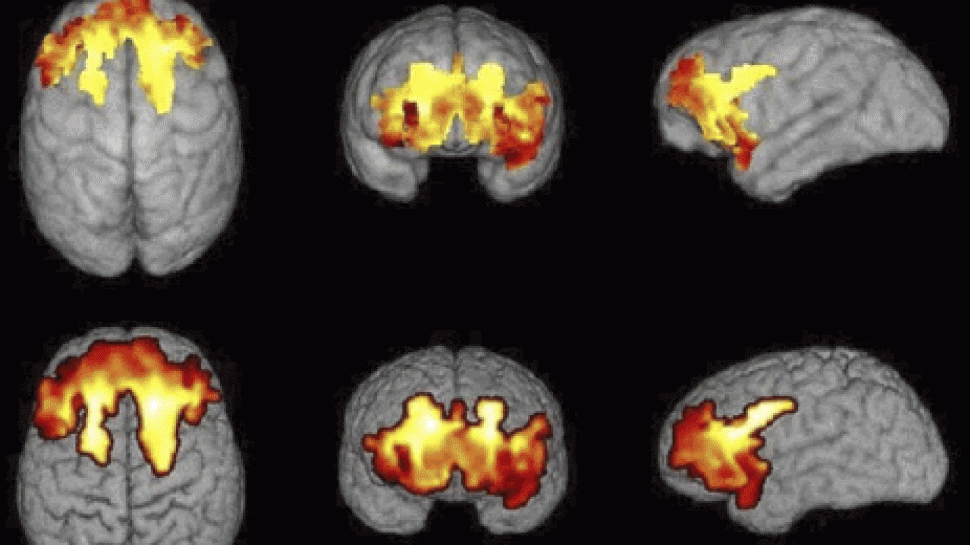

The study showed that socioeconomic conditions have a very big impact in the early period of brain development. Especially large differences were observed in the regions responsible for speech and reading, memory, decision-making ability and understanding of spatial relations.

Scientists compared the income and education of parents before using a scanner to measure the surface of the brain in children and teenagers. Then they compared the results of cognitive tests, taking into account other factors that may influence the development of the brain -- for example, genes.